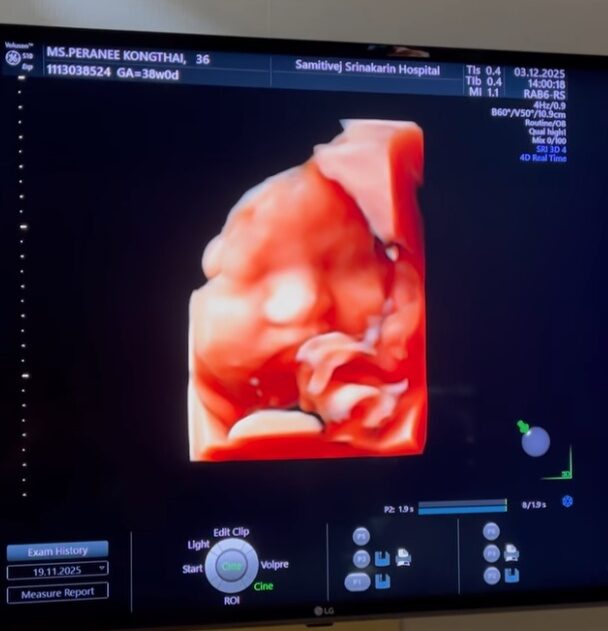

ตื่นเต้นกันทั้งว่าที่คุณพ่อคุณแม่ แมท ภีรนีย์ นางเอกสาวคนดัง และ เฟม ภีมเดช สามี ก่อนหน้านี้เมื่อสองสัปดาห์ ว่าที่คุณพ่อโพสต์คลิปสุดเห่อลูกชายขณะพาภรรยาไปอัลตราซาวด์ลูกน้อย พร้อมแคปชั่น ก็ลงคลิปลูกแบบรัวๆ พร้อมแคปชั่นว่า

“Completed 38 weeks pregnancy คุณแม่เก่งมากๆ ส่วนคุณลูกแน่นมากกกกคับ 3.2KG and keep on gaining มีการแลบลิ้นทักทาย พร้อมเมื่อไหร่ออกมาได้เลย ตื่นเต้นแล้วคับ” ทั้งคุณแม่และคุณยายก็เข้ามาคอมเมนต์กันตื่นเต้นมากๆ แทบจะรอไม่ไหวอยากจะต้อนรับสมาชิกตัวน้อย

ภาพลูกชาย แมท ภีรนีย์ ใกล้คลอดมากๆแล้ว